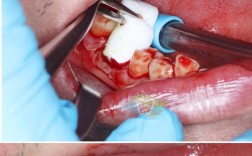

在骨引导技术方面,20年前的引导骨再生(GBR)技术刚刚兴起,所用的生物膜(如胶原膜、聚乳酸膜)阻隔软组织能力有限,稳定性较差,容易发生感染或膜暴露,导致植骨失败,医生往往需要通过“分层植骨+钛网支撑”等复杂方式维持骨空间,手术创伤大、术后恢复慢。

长期缺牙导致的严重骨吸收

后牙缺失数年甚至十年以上,牙槽骨因缺乏咀嚼刺激而垂直向和水平向吸收严重,剩余骨高度不足8mm、宽度不足5mm,此时直接种植可能导致种植体穿入上颌窦、下颌管等重要解剖结构,或因骨覆盖不足导致松动,医生需先进行“块状植骨”或“骨劈开术”,通过自体骨或骨替代材料重建骨量,待3-6个月骨愈合后再二期植入种植体。

即刻种植的骨量要求

即刻种植(拔牙后立即植入种植体)在20年前技术尚不成熟,仅适用于拔牙窝骨壁完整、无明显吸收的情况,若拔牙后存在骨缺损(如根尖残留、骨壁穿孔),需同期植骨填充拔牙窝,否则种植体周围易形成血肿,影响骨结合。